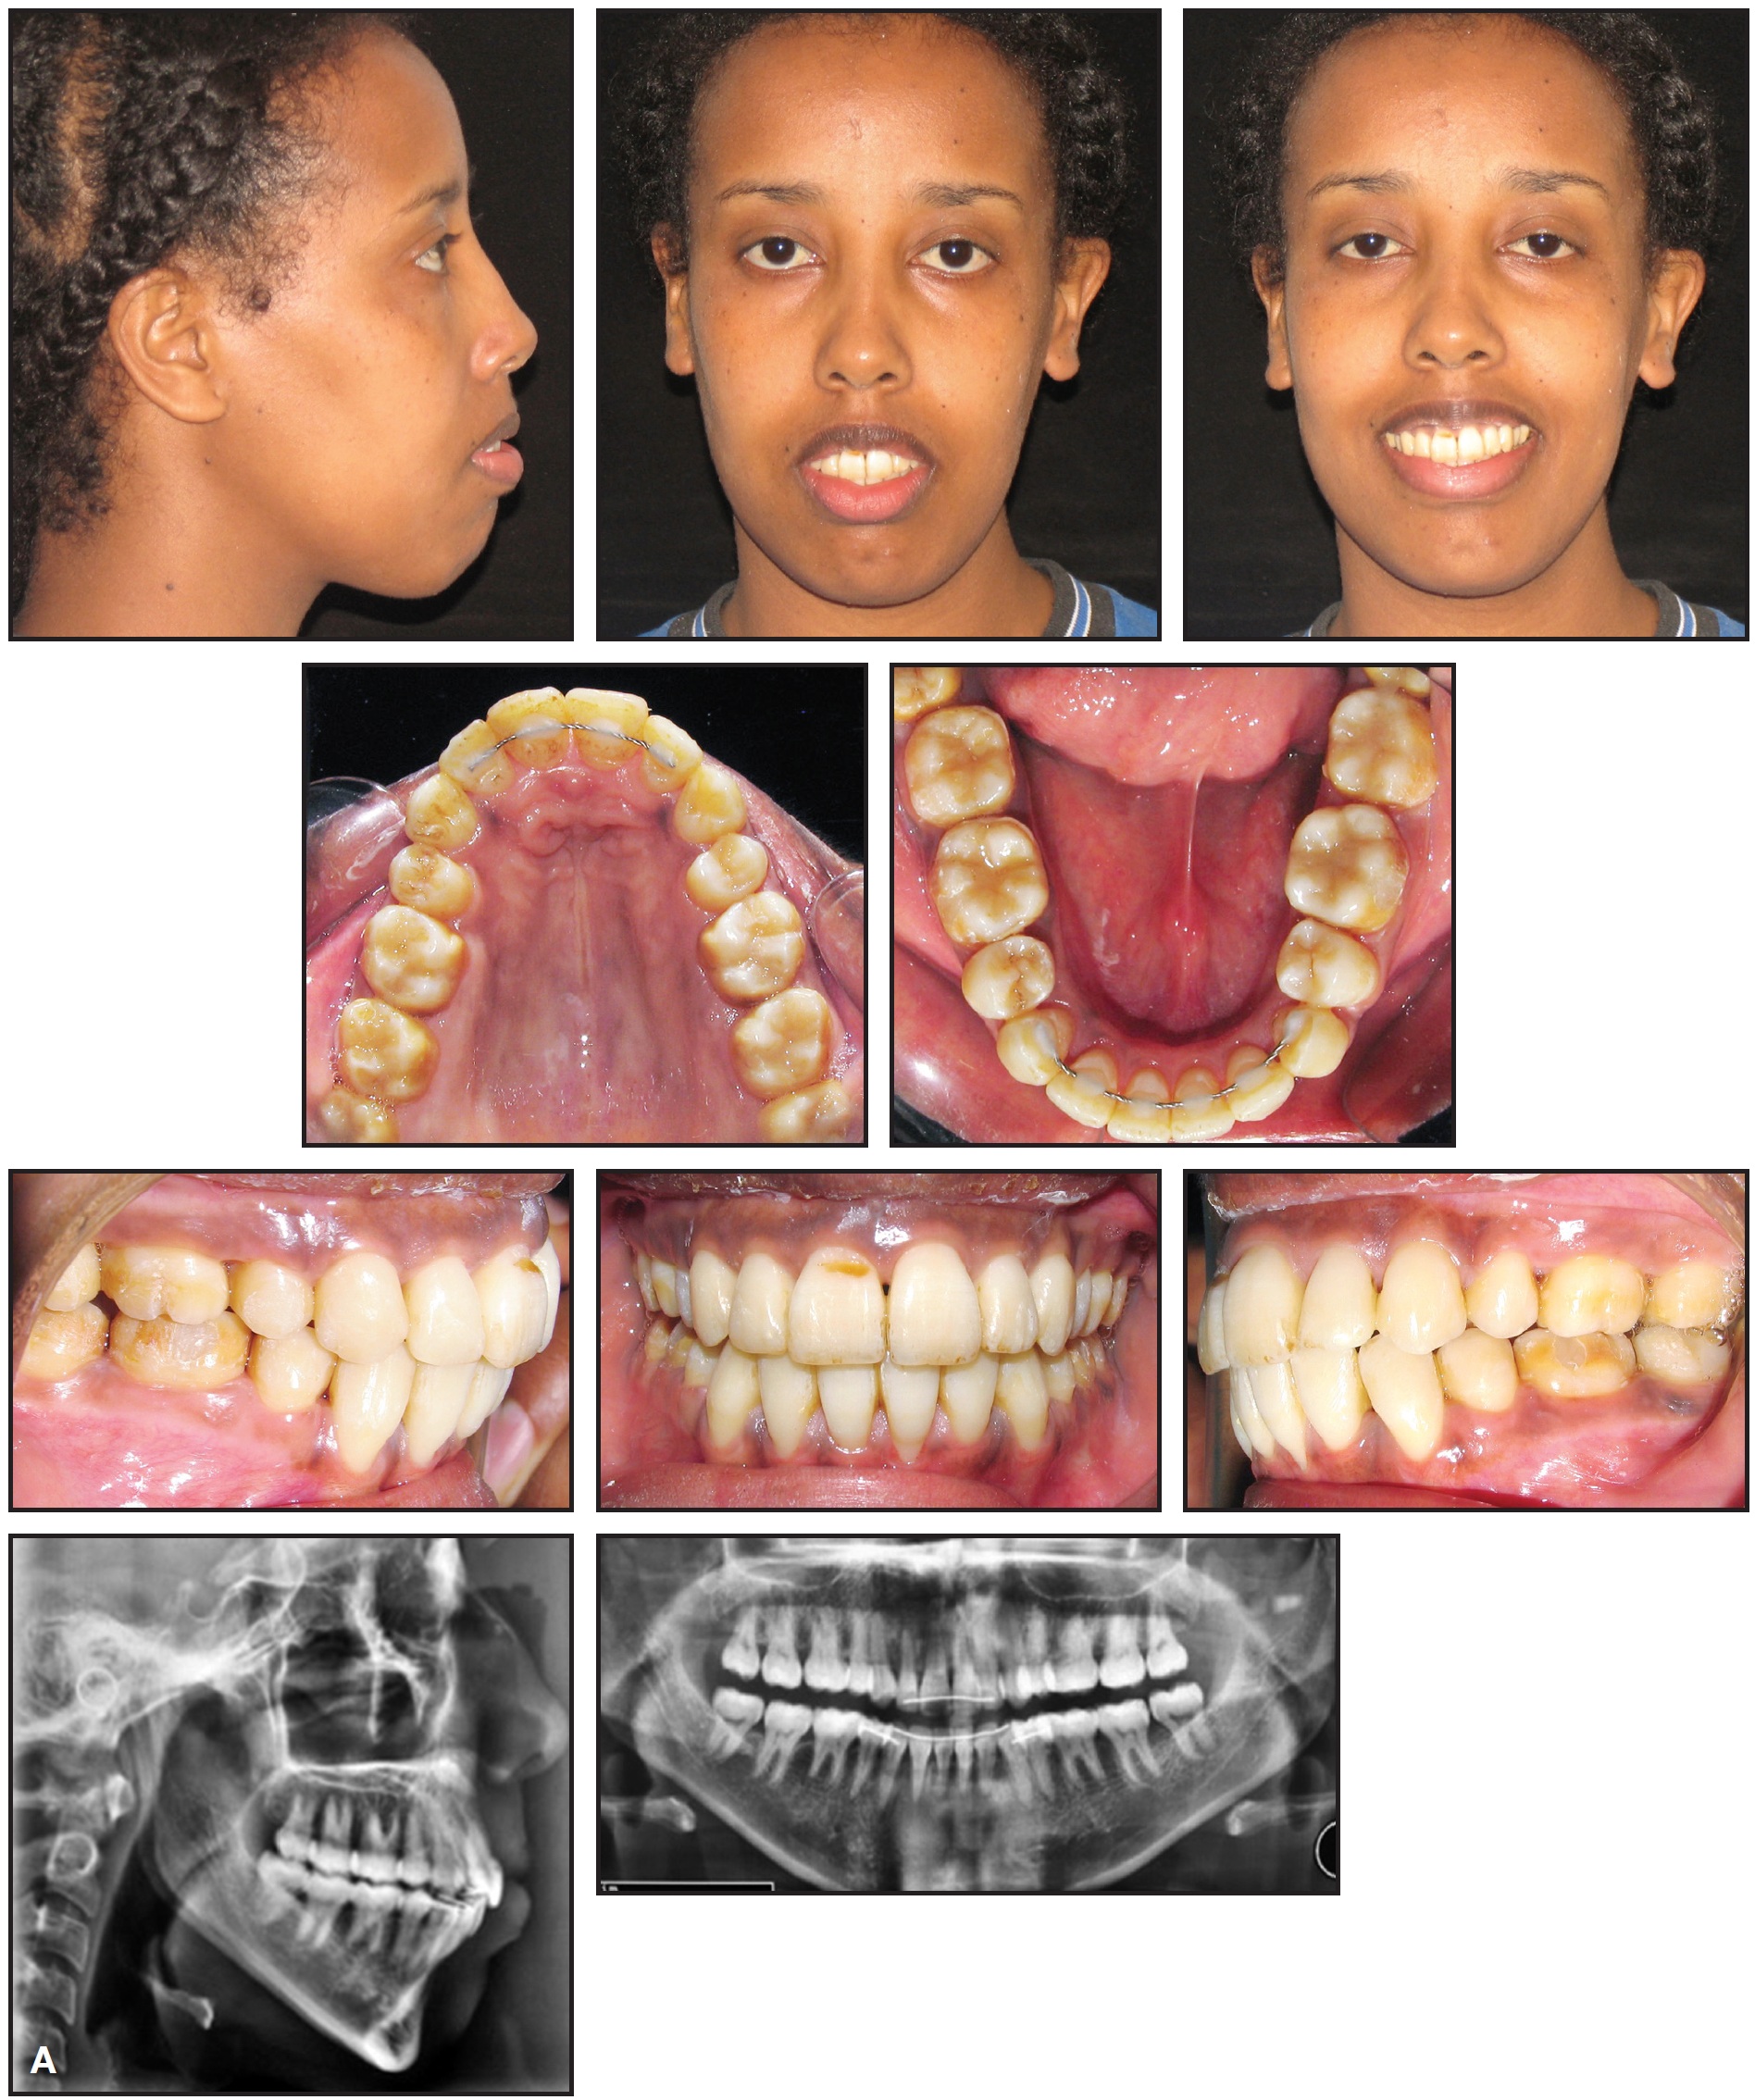

A 27-year-old female presented to the orthodontic department at Lebanese University with the chief complaints of proclined upper anterior teeth and crowding in the lower arch. She exhibited a convex profile, an acute nasolabial angle, excessive lower facial height, lip incompetency at rest, and inadequate extension of the chin (Fig. 1). On smiling, she displayed the lower incisors and less than the full crowns of the upper incisors.

Fig. 1 27-year-old Class II female patient with severe lower crowding, 10mm anterior open bite, and severe hyperdivergence before treatment.

Fig. 1 (cont.) 27-year-old Class II female patient with severe lower crowding, 10mm anterior open bite, and severe hyperdivergence before treatment.

The intraoral photographs and dental casts revealed an anterior open bite of 10mm and an overjet of 15mm. In addition, two distinct occlusal planes were present in the upper arch. The lower arch had severe crowding, with the canines completely blocked out and the left first premolar and a supernumerary premolar blocked in. The upper dental midline was aligned with the facial midline, but the lower midline was deviated 2mm to the right. Sagittally, the molars were in a 2mm Class III relationship, the right canine was in a Class III relationship, and the left canine was in a full Class II relationship.

The patient was a mouth-breather and had a tongue thrust at rest. TMJ examination revealed clicking on both sides, with bayonet closure but no pain. Radiography showed a restoration at the level of the lower right first molar, as well as mesially inclined lower canines and premolars.

Cephalometric analysis indicated a skeletal Class II relationship with bimaxillary protrusion (Table 1).

The mandibular plane angle was steep, and the gonial angle was severely increased (MP-FH = 39 degrees). The upper incisors were extremely proclined; the lower incisors were retroclined. Treatment objectives were to correct the convex profile, reduce the lower facial height, widen the maxilla to ameliorate the V-shape archform, relieve the crowding, and achieve a Class I relationship with ideal overjet and overbite.